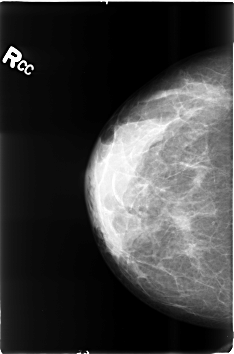

B_3497_1.RIGHT_CC

RIGHT_CC LINES 4600 PIXELS_PER_LINE 3032 BITS_PER_PIXEL 12 RESOLUTION 50 NON_OVERLAY